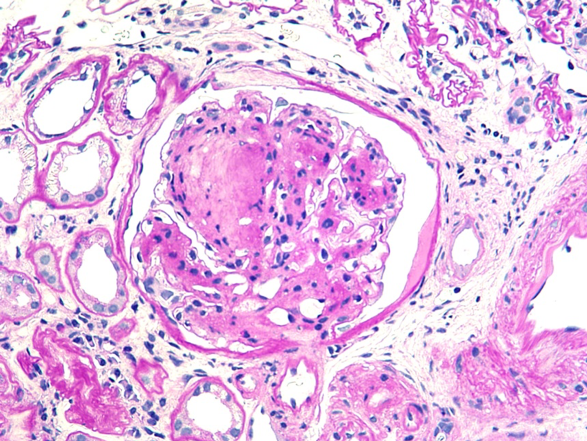

糖尿病の既往のない患者に実施した腎生検で以下の糸球体病変がみられた。鑑別診断に有用でないのはどれか。1つ選べ。

| a | タンパク尿量 |

| b | 喫煙歴 |

| c | 蛍光抗体法 |

| d | 電子顕微鏡所見 |

| e | 尿中ベンスジョーンズ蛋白 |